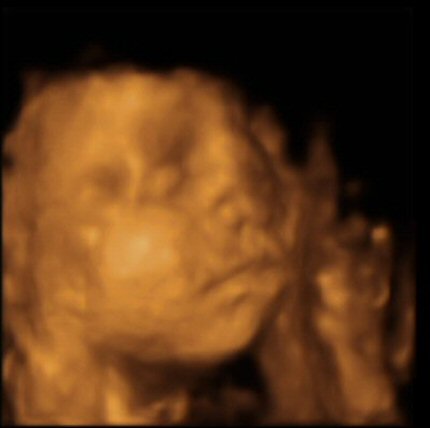

- The scan photos shown below are 3D images from the babybond 4D scan at 29 weeks gestation.